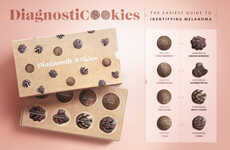

The 'Get Your Butt Seen' Print Ads for Colorectal Cancer Raise Awareness

These amazing 'Get Your Butt Seen' print ads for the Colorectal Cancer Association of Canada (CCAC) are eye-catching and informative. The ads feature a series of naked bums to draw attention to cancers below the belt.

I love this idea for an ad campaign -- not only is it in your face, but it raises cancer awareness in general. The CCAC is a great charity that aims to find a cure for colon cancer using these hilarious print ads.

I love this idea for an ad campaign -- not only is it in your face, but it raises cancer awareness in general. The CCAC is a great charity that aims to find a cure for colon cancer using these hilarious print ads.

Cancer Awareness Ads — Print ads and campaigns that focus on raising awareness and promoting early detection of various types of cancers can help in the fight against these diseases.